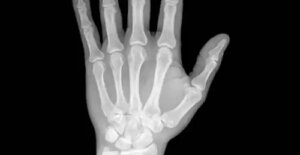

În general, primele simptome ale acestei boli sunt durerea la nivelul articulațiilor și dificultatea de mișcare a acestora. Unul dintre simptomele caracteristice este rigiditatea articulațiilor dimineața, care durează mai mult de 60 de minute și se ameliorează pe parcursul zilei. Cele mai afectate articulații sunt:

- Mâinile

- Degetele

Artrita reumatoidă determină inflamarea articulațiilor și a țesuturilor. Din acest motiv, mișcarea normală a corpului este dificilă. Este o boală autoimună, ceea ce înseamnă că organismul se atacă singur din greșeală.

De asemenea, prezintă adesea arsuri, roșeață și deformarea articulațiilor. Pacienții simt amorțeală în mâini și picioare și pot avea și alte boli, cum ar fi sindromul de ochi uscat.